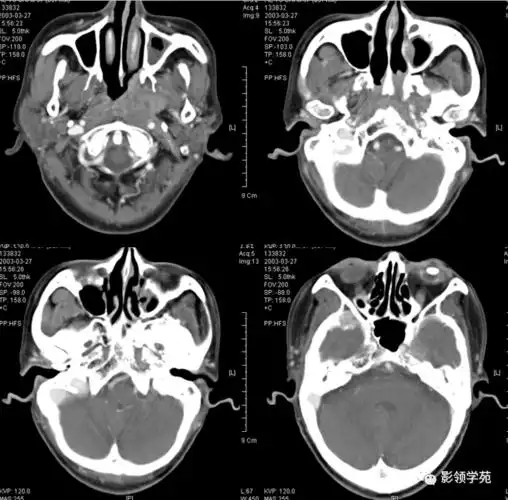

头颈部ct断层解剖图谱

颞骨正常ct解剖-轴位